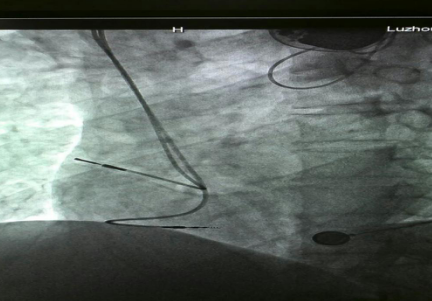

已安裝好的起搏系統(tǒng)

在征得患者及家屬的同意后,我院為其實施了雙腔永久心臟起搏器植入術,該手術在瀘州市市屬醫(yī)院中率先使用磁共振兼容起搏電極,為患者未來有可能接受的磁共振檢查創(chuàng)造了條件。